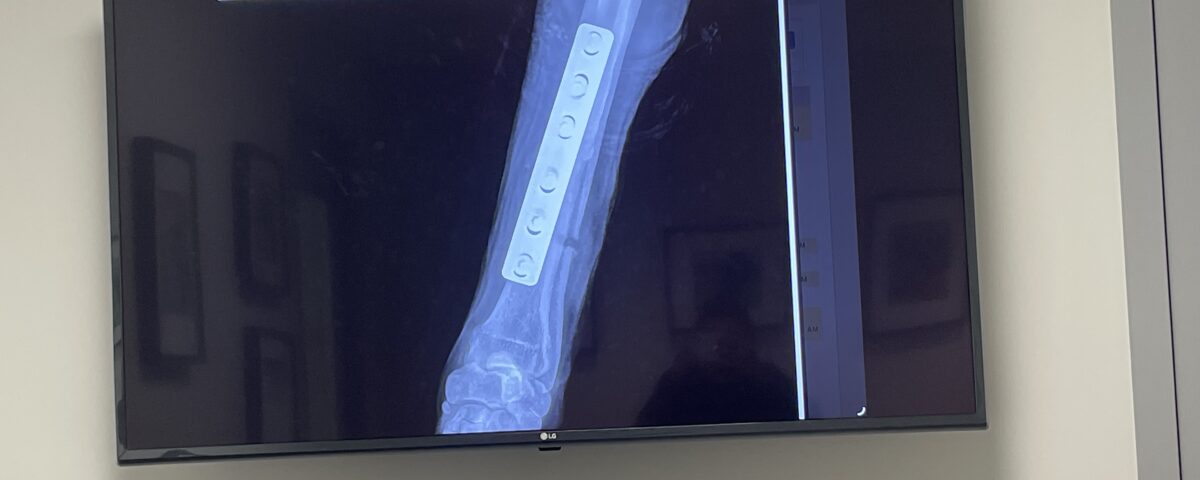

Sierra’s broken leg